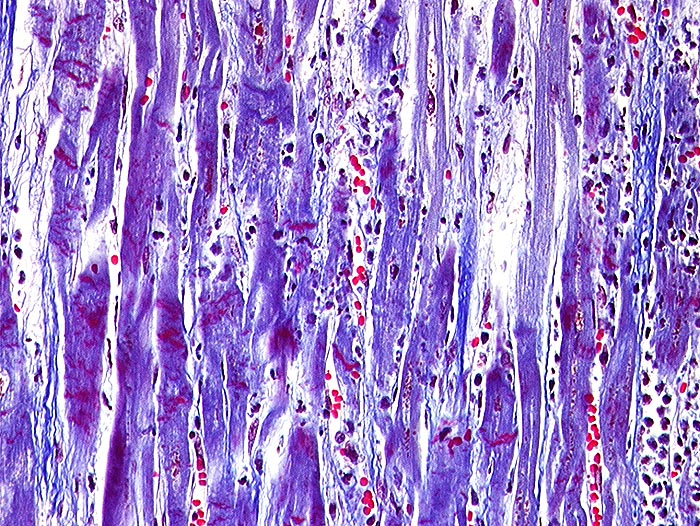

Akuter Myokardinfarkt: Kontraktionsbänder

Quer zu den Myozyten verlaufende rot gefärbte Kontraktionsbänder. Granulozytäres Infiltrat rechts im Bild.

Kontraktionsbänder sind nach 30 Minuten, zelluläre Infiltrate nach minimal 3 Stunden sichtbar. Kontraktionsbänder entstehen, wenn das hypoxisch geschädigte Myokard sich noch kontrahiert, aber nicht mehr relaxieren kann.